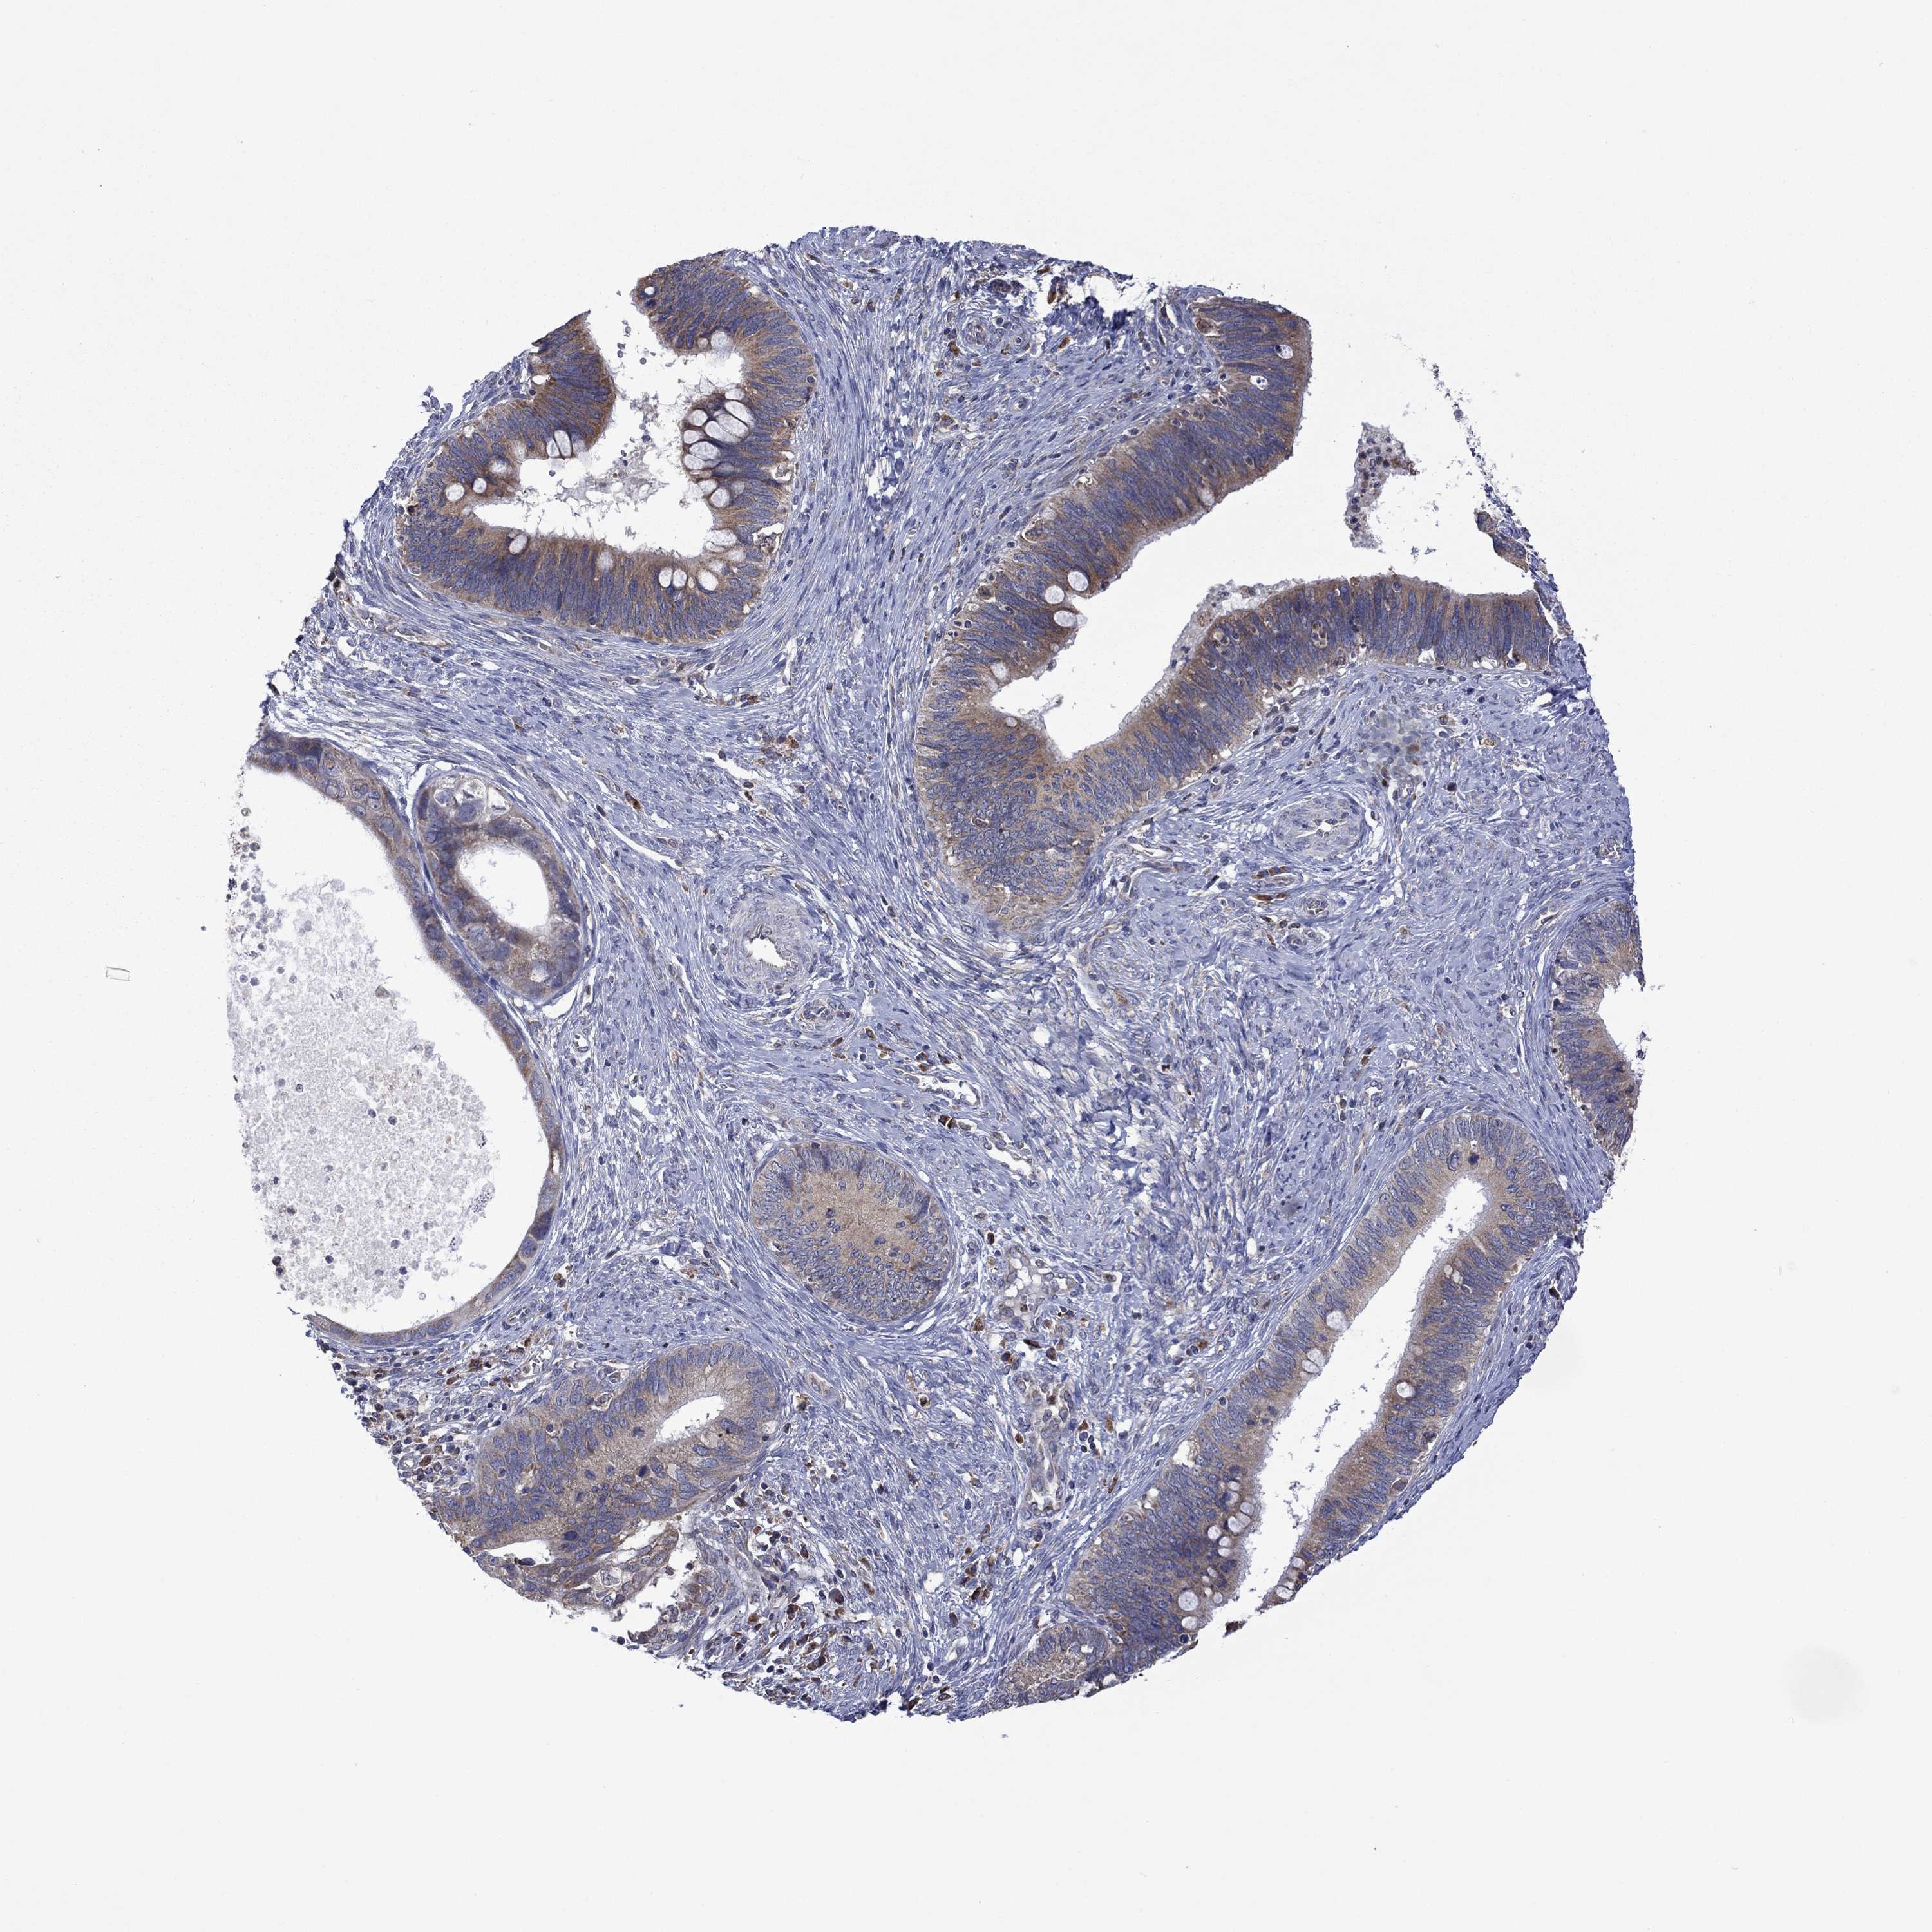

CERVICAL CANCER - Protein expressioni

A mouse-over function shows sample information and annotation data. Click on an image to view it in a full screen mode. Samples can be filtered based on level of antibody staining by selecting one or several of the following categories: high, medium, low and not detected. The assay and annotation is described here.

Note that samples used for immunohistochemistry by the Human Protein Atlas do not correspond to samples in the TCGA dataset.

Antibody stainingi

Antibody staining in the annotated cell types in the current human tissue is reported as not detected, low, medium, or high, based on conventional immunohistochemistry profiling in selected tissues. This score is based on the combination of the staining intensity and fraction of stained cells.

Each image is clickable and will lead to virtual microscopy that enables deeper exploration of all samples and also displays staining intensity scores, fraction scores and subcellular localization as well as patient and tissue information for each sample.

Antibody HPA067869

Antibody CAB009499

Staining

High

Medium

Low

Not detected

Intensity

Strong

Moderate

Weak

Negative

Quantity

>75%

75%-25%

<25%

None

Location

Nuclear

Cytoplasmic/membranous

Cytoplasmic/membranous,nuclear

Squamous cell carcinoma, NOS

Adenocarcinoma, NOS